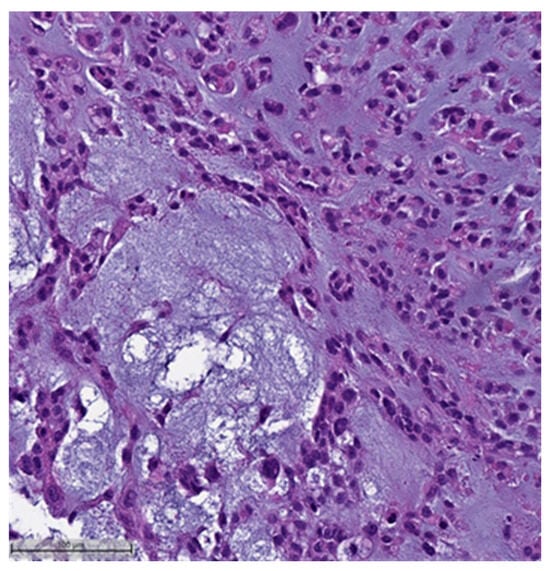

This system is primarily based on the specific metaplastic elements present within the tumors, while also highlighting the potential overlap that can exist between various histological subtypes [6]. Consequently, numerous cases diagnosed as MpBCs, are accompanied by a detailed description of the histological component or a combination of different component types and/or differentiations. The following figures illustrates a few examples: spindle cell carcinoma component with pleomorphic features (Figure 4), metaplastic breast carcinoma with chondroid differentiation (Figure 5), metaplastic breast carcinoma with a matrix-producing component (Figure 6), metaplastic breast carcinoma with osseous differentiation (Figure 7), and extensive trabeculae bone and hematopoietic tissue (Figure 8).

Figure 4.

Spindle cell carcinoma component with pleomorphic features (H&E, 20×).